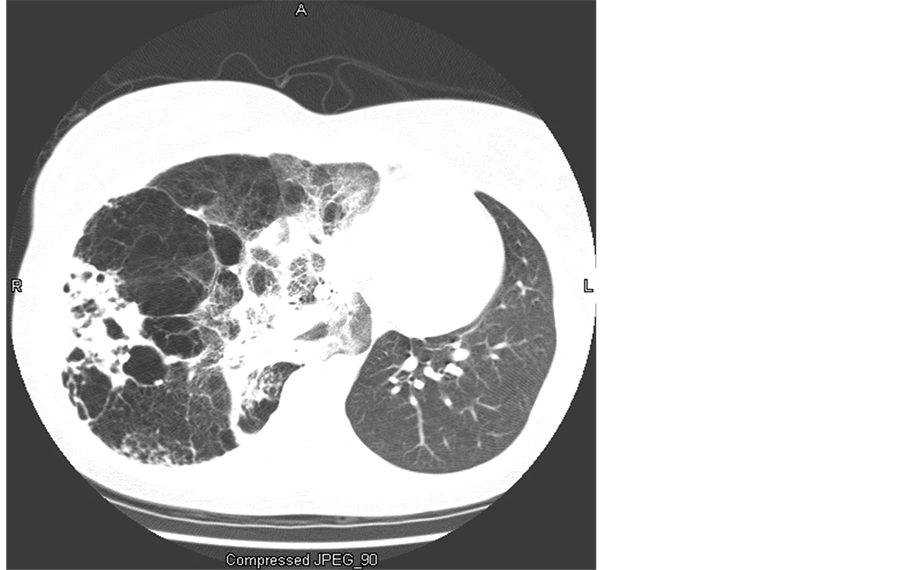

On presentation to our institution, a chest radiograph indicated a hyper-expanded right lung with right-to-left mediastinal shift, right basilar fibrosis with an air-fluid-filled cyst in the right lower lung field, and an inferiorly displaced right hemidiaphragm. A CT of the chest demonstrated a severe hyperinflated, emphysematous right upper and middle lung, partial preservation of the right lower lung with diffuse fibrosis, nodules and cystic air-fluid-filled cavities, and small but patent right main stem bronchus and pulmonary artery (Figure 1). The left lung was small with normal appearing parenchyma. Pulmonary function tests showed restriction (TLC 66% predicted) without obstruction (FVC 59%, FEV1 52% predicted), and decreased diffusion (DLCO 57% predicted). An echocradiogram depicted normal chamber dimensions with preserved systolic and diastolic function without evidence of pulmonary hypertension. A scintigraphic ventilation perfusion scan determined the right lung to be responsible for 15.9% of the ventilation and 11.5% of the perfusion, corresponding to a matched defect.

Figure 1. Chest computed tomography demonstrating hyper-inflated, cystic and fibrotic right lung changes.